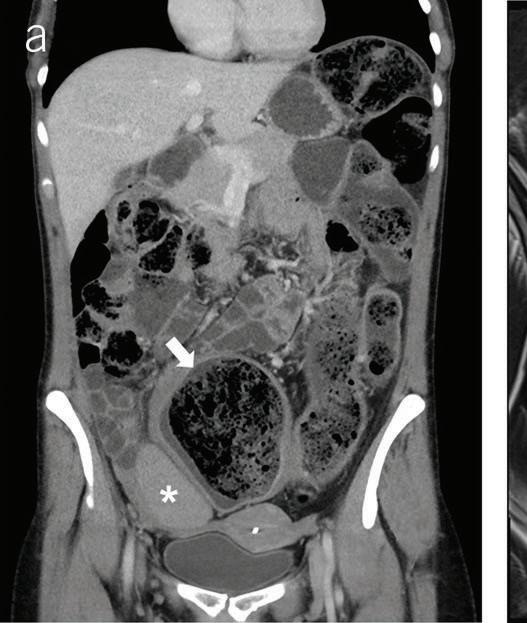

In a 1991 report in The American Journal of Gastroenterology, Drs. Alemayehu and Järnerot challenge prior orthodoxy that colonoscopy is contraindicated in patients with severe ulcerative colitis.